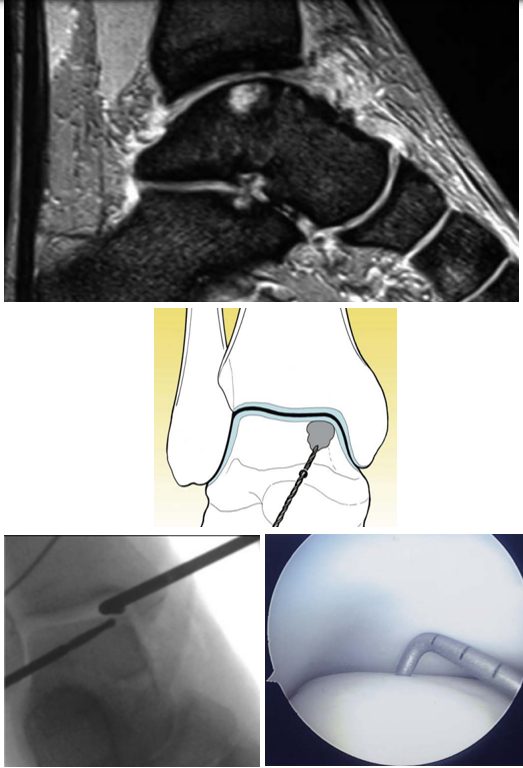

Рис. 14. Ретроградная туннелизация таранной кости

Техника (артроскопическая):

- Диагностическая артроскопия через стандартные порталы (передне-медиальный рабочий, передне-латеральный обзорный)

- Идентификация и оценка ОХП пробником

- Дебридмент: удаление нестабильного хряща малой кюреткой. Стабильные края хряща сохраняются и формируются вертикально (perpendicular) для удержания кровяного сгустка

- Удаление склеротической субхондральной пластинки кюреткой

- Микрофрактуринг: перфорация субхондральной кости шилом (awl, обычно 60-65°) перпендикулярно поверхности. Отверстия на расстоянии 3-4 мм друг от друга. Глубина — до появления жировых капель (fat droplets), что подтверждает проникновение в костный мозг

- Снижение давления ирригации → визуализация кровотечения из перфорационных отверстий (подтверждение эффективности)

- Формирование стабильного кровяного сгустка (super clot)

Рис. 10. Артроскопическое микрофрактурирование субхондральной пластинки